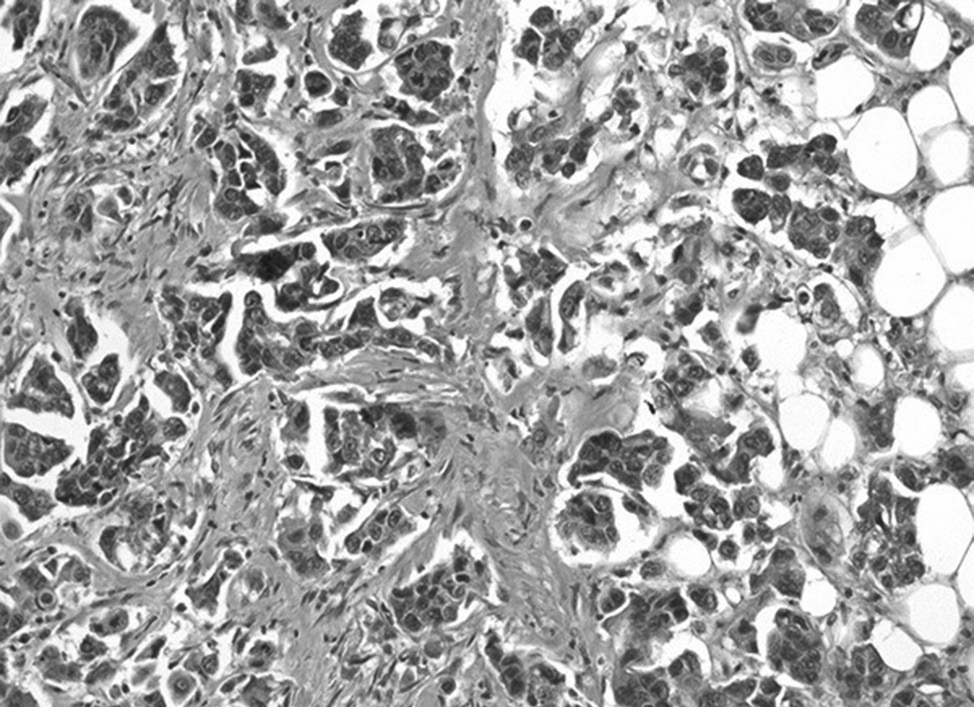

Aim of the study is to demonstrate a unique case report: synchronous malignant tumors of the breast and kidney with tumor to tumor metastasis.

Materials and methods. The analysis of medical history and the pathology study of surgical material using histological and immunohistochemical methods was carried out.

Results. Clinical observation of metastasis of triple-negative breast cancer in a synchronous renal cell carcinoma of the kidney in a 59-year-old woman has been described. Tumor to tumor metastases are diagnosed by a remote kidney with a neoplasm, hematuria, anemia, and thrombocytopenic syndrome manifested in the clinic.